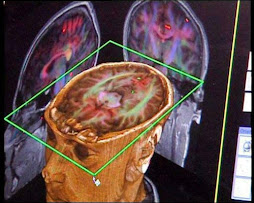

Cortes axial y coronal de los HC señalando la ubicación de los núcleos basales, la capsula interna y corona radiante.

Esta practica me pareció interesante y muy dentretenida ya que con los modelos anatómicos y también con las placas de RMI de los hemisferios cerebrales pudimos identificar y entender mejor el objetivo de la misma ya que es muy importante el observar y no solo leer, en esta sesión estudiamos lo que son las circunvoluciones, además de las cisuras del encéfalo y cada uno de sus nombres.